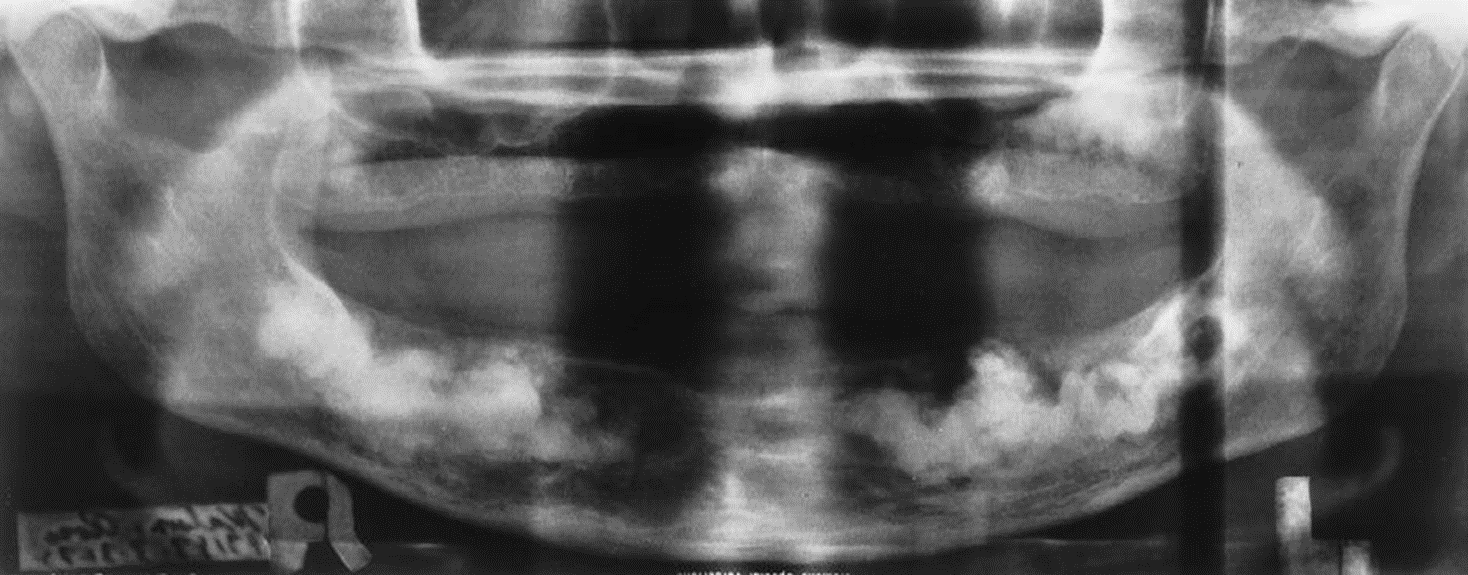

3. This is a 35-year-old asymptomatic woman who has slight buccal and palatal enlargement of the alveolar bone in this area. Other studies indicated portions of the zygoma were involved. This condition was first detected at age 19 years and is slowly progressive. Her alkaline phosphatase was normal to high-normal, and her serum calcium was normal.

What is your diagnostic impression?